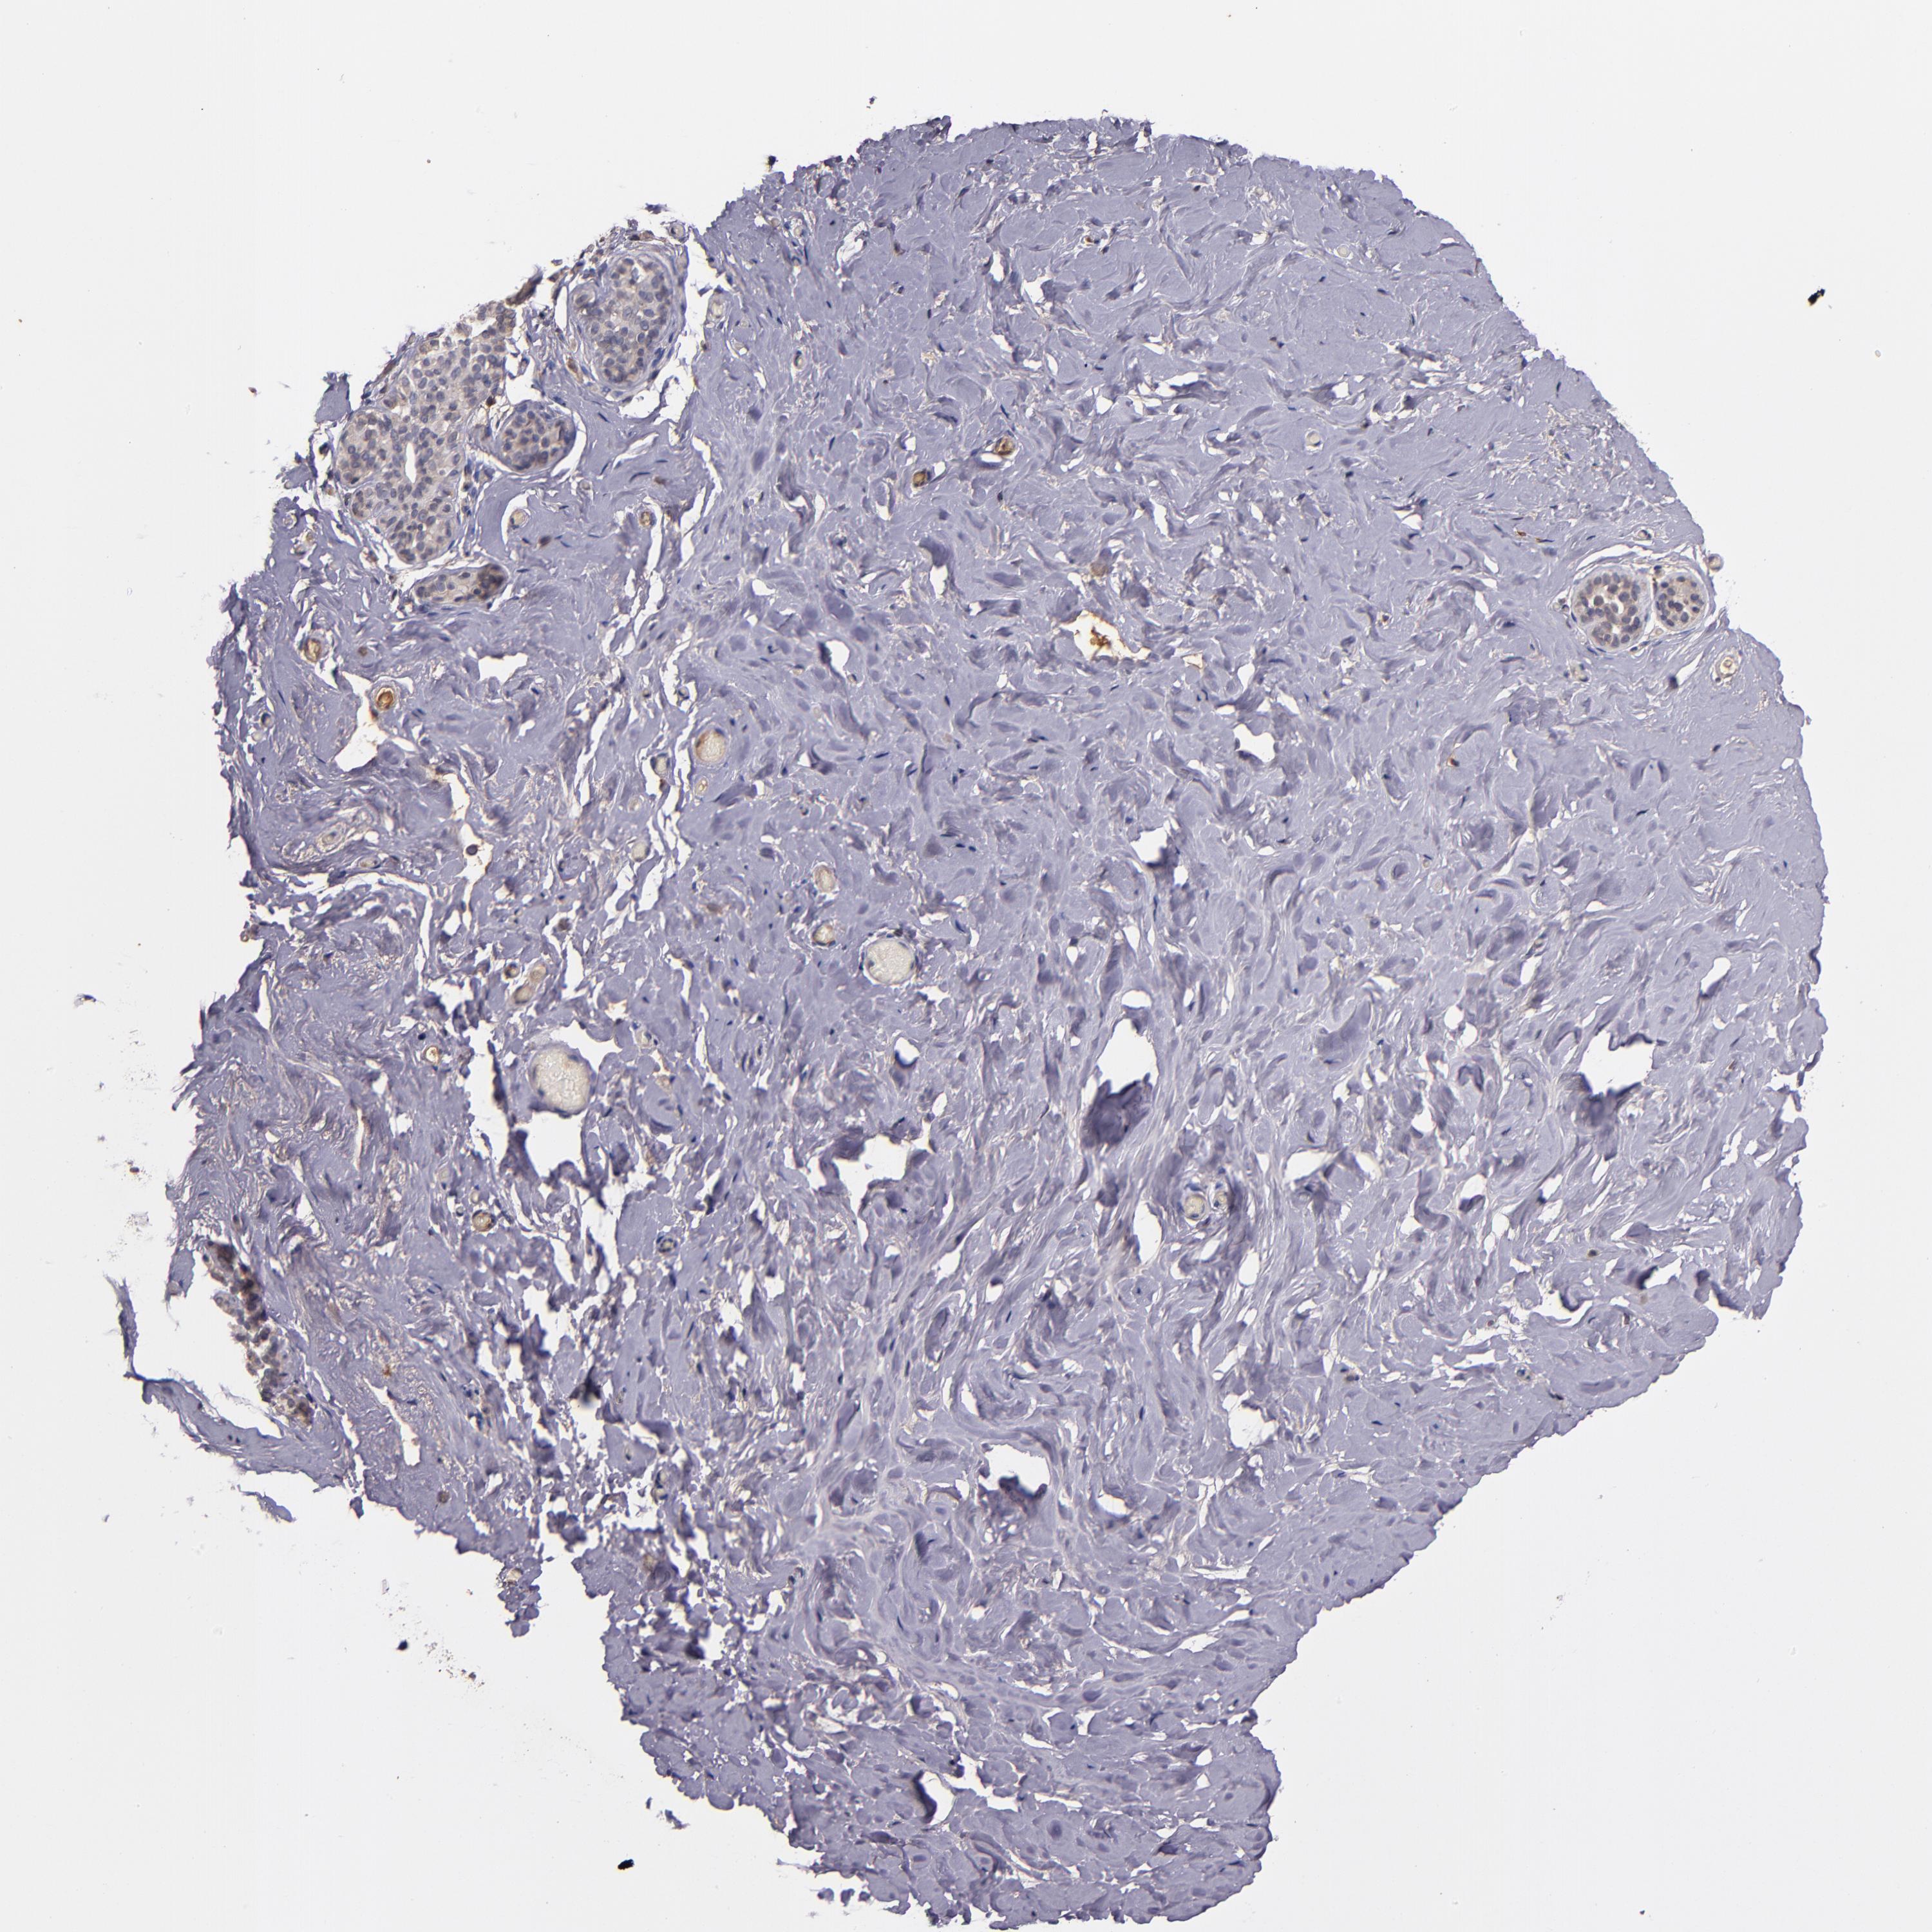

BREAST - Antibody stainingi

Antibody staining in the annotated cell types in the current human tissue is reported as not detected, low, medium, or high, based on conventional immunohistochemistry profiling in selected tissues. This score is based on the combination of the staining intensity and fraction of stained cells.

Each image is clickable and will lead to virtual microscopy that enables deeper exploration of all samples and also displays staining intensity scores, fraction scores and subcellular localization as well as patient and tissue information for each sample.

Antibody HPA002859Antibody CAB011655

Adipocytes -Not detected

Glandular cells Not detectedLow

Myoepithelial cells Not detectedLow